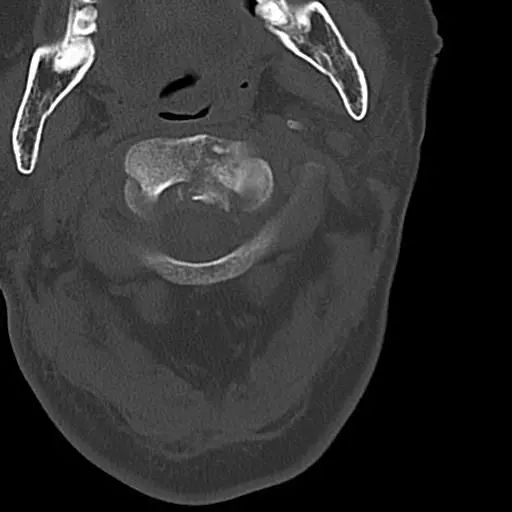

患者,男性,75岁,因外伤致颈部疼痛伴活动受限7天入院。患者入院前在当地医院确诊为:枢椎齿状突骨折Anderson-D’Alonzo分型Ⅱ型。

对于本患者来说,齿状突骨折后导致寰枢椎不稳,极易引起延髓或椎动脉损伤,严重者当场死亡。但患者同时合并严重胸腰椎后凸畸形,颈部后伸受限,不具备前路手术条件,这就给其治疗更增加了额外的困难。而由于手术部位延髓及椎动脉等血管神经密布,手术难度高、风险极大,稍有不慎,患者就会有生命危险。而患者家属在了解到手术的危险性后,曾自行到上级医院咨询专家,上级医院专家考虑围手术期死亡的风险,对于本例患者亦不愿提供手术治疗的机会。

经过全程监护和系统治疗,患者术后恢复良好,骨折解剖复位,复查X线及CT显示固定位置佳,术后3天下地行走,术后4天即出院回家休养。